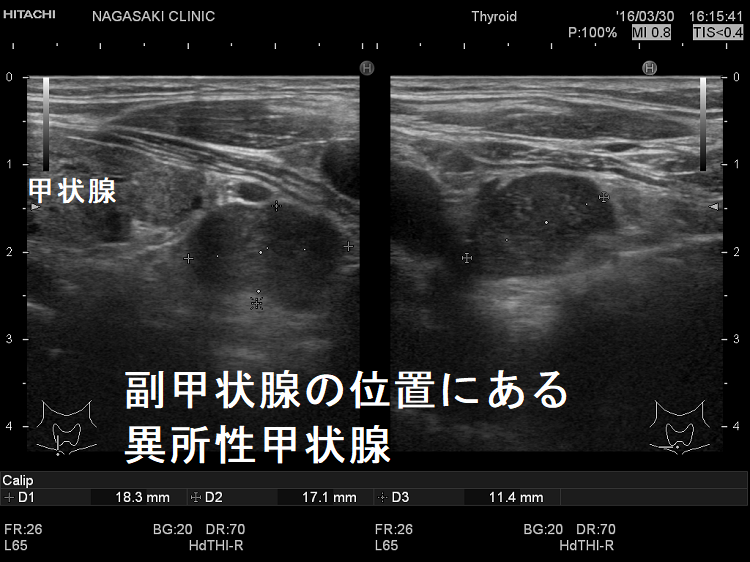

副甲状腺腺腫のように見えるも、実は異所性甲状腺

副甲状腺腺腫と同じような位置(写真では右甲状腺の下極)にあり、副甲状腺腺腫のように見えるも、実は頚部異所性甲状腺です。

副甲状腺腺腫との違いとして、頚部異所性甲状腺では

- 内部血流が甲状腺組織と同じ

- 内部の形状が甲状腺組織と同じ

です。